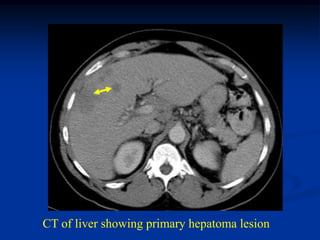

Case #1155.1                    Metastatic Hepatoma

9/9                 9/26              10/21

51 yr male with pain 3 wks prior to fracture of humerus

Axial T-1 MRI   Bone scan

CT of liver showing primary hepatoma lesion